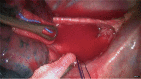

The tracheal and bronchial stump before anastomosis.

Figure 9